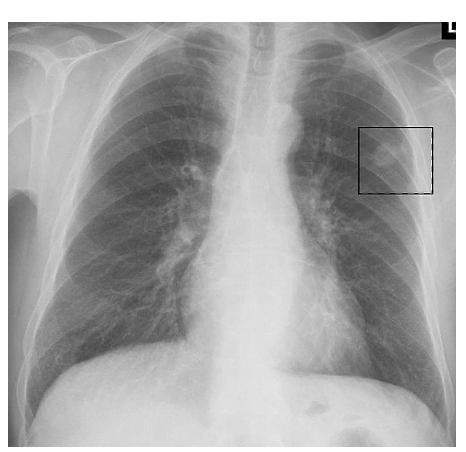

Chest X-ray – this may reveal a mass